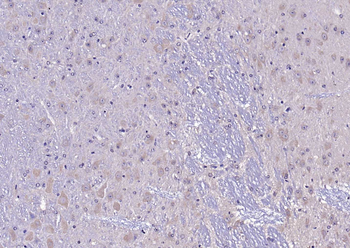

Immunohistochemical staining of human colon cancer using TRPV1 antibody